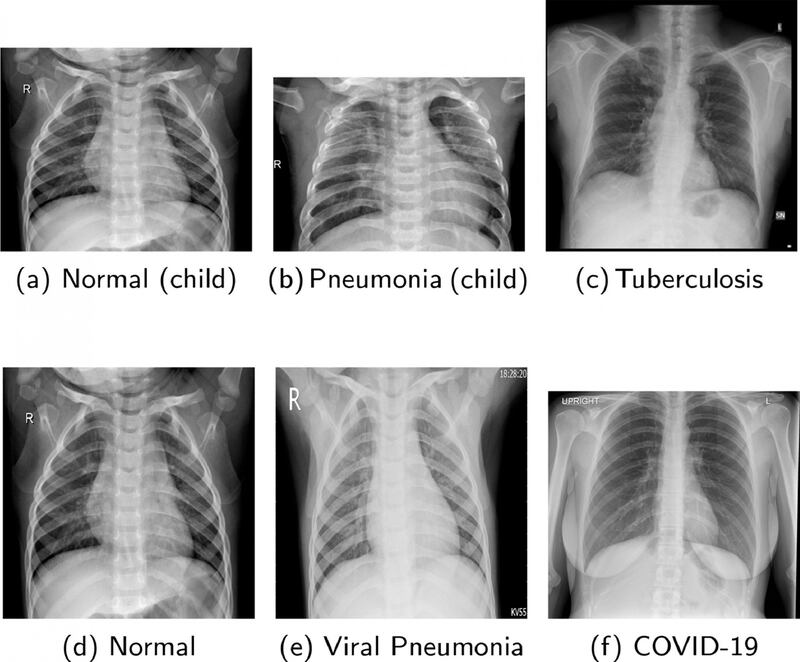

El equipo creado por la UWS usa imágenes de rayos X, comparándola con una base de datos de miles de imágenes de pacientes con neumonía, tuberculosis y COVID-19.

En este caso, el entrenamiento consiste en que el software analice miles de imágenes de radiografías de pacientes.

Mediante la red neuronal convolucional profunda, se comparan imágenes, determinando la existencia o no de alguna enfermedad.